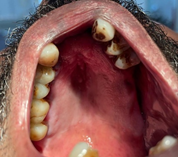

Vital signs were within normal limits. Extra oral examination revealed facial asymmetry (deviation to the left side) with other associated craniofacial abnormalities including a small receding chin indicative of micrognathia, maxillary hypoplasia, depressed frontal bone with prominent eyebrows, exophthalmos, slanting palpebral fissure and a left malar hypoplasia (Figure 2). The mouth opening was normal with a deflection towards the left side. Intraoral examination revealed incomplete cleft palate, and generalized periodontitis with multiple teeth missing (Figure 3).

Figure 3 Intraoral view showing incomplete cleft palate, generalized periodontitis, and multiple missing teeth.